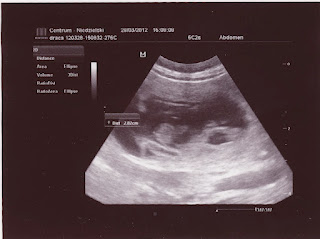

Ale śliczne fasoli. Widzę, że minimum 2 są .

Za tydzień idziemy na kolejne USG więc może dopatrzymy się więcej, ale w 21 dniu nie mogliśmy wypatrzyć więcej.

Jakie fajne malutkie głowki, i kręgosłupki:D